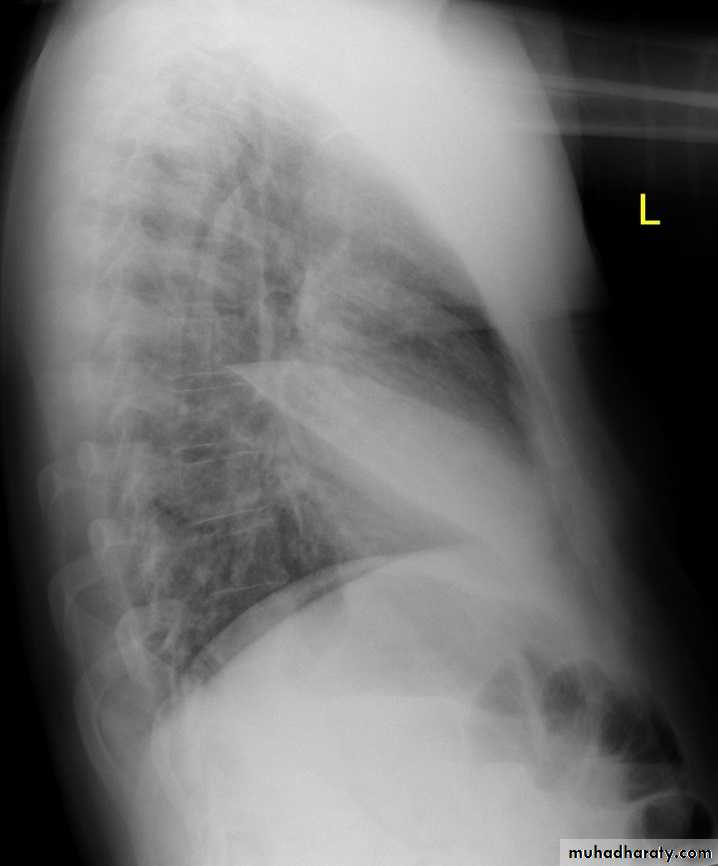

This cut-out of a lateral chest x-ray shows the positions of the lobes of the right lung

On the left the oblique fissure is in a similar position but there is usually no horizontal fissure, and so there are only two lobes on the left.